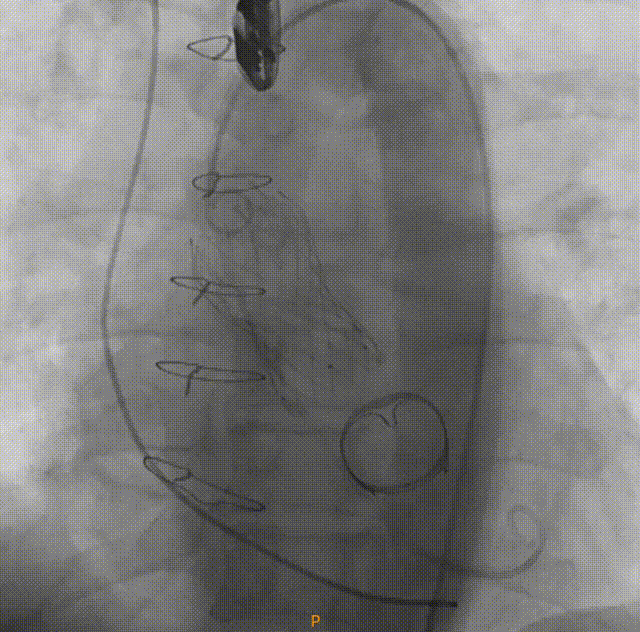

在虚拟主动脉瓣环下10 mm左右可见二尖瓣生物瓣,因为左室流出道锚定区域有限,瓣膜系统的释放位置需要格外关注,一旦植入位置不当或瓣膜下滑位置偏深,将影响二尖瓣生物瓣瓣叶的正常开合,但如果释放位置太高或牵拉力量过大,容易导致瓣膜释放时弹出,手术难度极高;

对于这样挑战的复杂病变,使用VenusA-Plus®可回收输送系统,为手术增加了一重保障,拟选择L29型号瓣膜经由右侧股动脉入路,选择标准位偏高2mm左右进行释放完成手术。瓣膜释放过程中,观察瓣膜位置,当瓣膜植入位置不合适,可以及时回收,重新调整位置再次释放,降低手术风险,提高手术成功率。

在放射科,超声科和麻醉科的通力协作下,顺利完成了术前准备,术者团队在术中谨慎建立轨道,根据主动脉根部造影的结果,初步判断释放体位是否合适观察瓣叶活动度、是否合并反流,选择合适的跨瓣体位。瓣膜释放前优先确认猪尾管位置,避免瓣膜在释放过程中脱载。